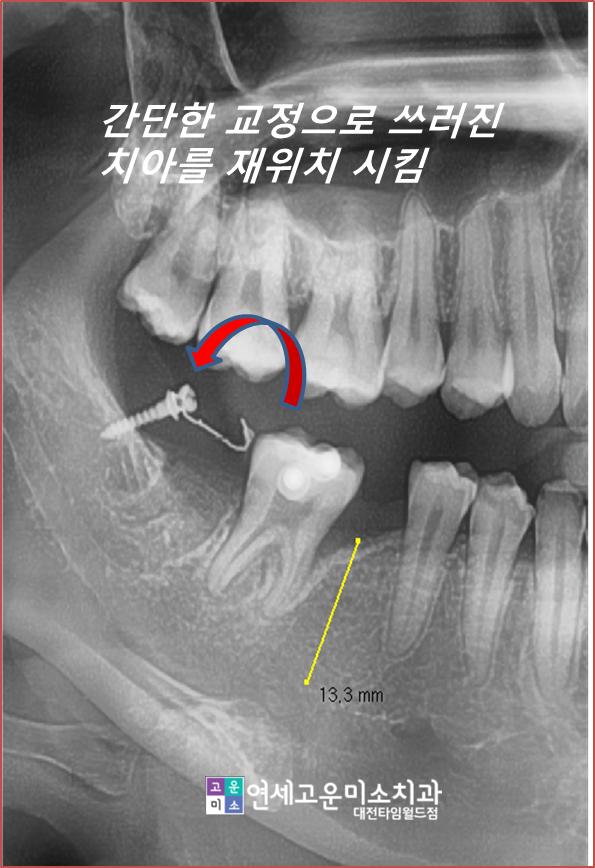

이런 경우 간단한 부분교정을 통해서

쓰러진 치아를 세우고

공간을 확보한 후

임플란트를 심을 수 있습니다.

전혀 보이지도 않고 기간도 오래 걸리지 않습니다.

완성된 모습입니다

쓰러진 치아도 세워졌고

임플란트도 옆의 치아들 뿌리와 평행하게

심을 수 있게 되어 저작에도 유리한 상황입니다.

일련의 치료 과정입니다

막연한 교정에 대한 두려움 때문에

이런 경우 신경치료를 하고 씌우시는 경우가

진짜 많습니다.

시간을 조금만 투자한다면 소중한 치아를

보존하면서 임플란트를 심을 수 있습니다.